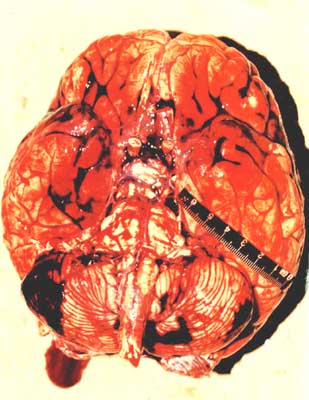

脑结构解释:吸毒者的大脑存在异常

2010年6月,长沙中南大学湘雅二医院精神卫生研究所研究人员采用最新脑影像学技术,对慢性K粉成瘾者进行了脑结构和脑功能活动改变研究,最终发现了K粉成瘾者前额叶脑白质、脑灰质的损害,其结构损害与精神分裂症患者的脑结构损害极为相似。这项发现在国际上尚属首次,它说明吸毒与大脑结构异常是有一定联系的。…[详细]